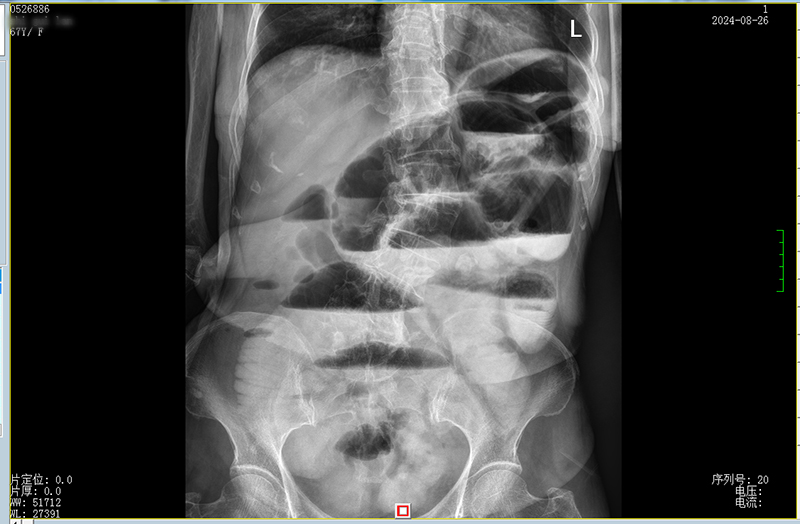

周女士在家属陪同下到我院就诊,门诊拟“肠梗阻”收住胃肠外科、减重代谢外科。完善检查后,科主任韦建宝主持了疑难病例讨论,周女士被诊断为子宫内膜癌手术后、放疗化疗后复杂性肠梗阻(图1),有手术治疗指征,韦建宝主任强调运用损伤控制性外科理念、根据术中情况选择合理的手术方式。

图1 消化道造影提示肠梗阻